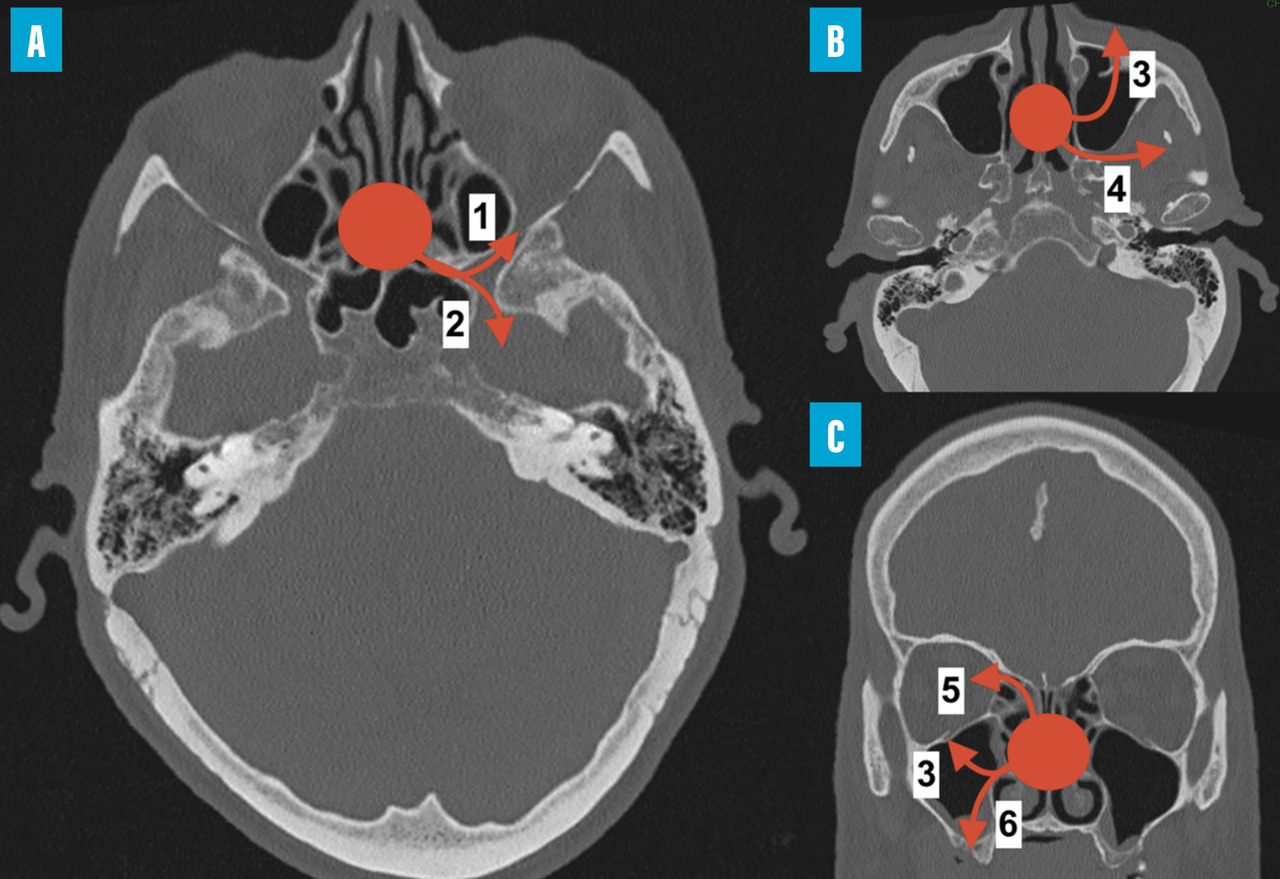

Le bilan comprend une imagerie par résonance magnétique (IRM) pour l’évaluation des tissus mous et une angio-tomodensitométrie (angio-TDM) pour rechercher une atteinte vasculaire. L’évolution de l’infection est en effet marquée par un angiotropisme. L’envahissement du sinus caverneux est une complication fréquente qui peut aboutir à un anévrisme mycotique de la carotide interne. L’envahissement de l’artère sphénopalatine peut entraîner l’invasion de la fosse infratemporale. L’extension depuis l’ethmoïde peut se faire vers l’orbite – induisant baisse d’acuité visuelle, ophtalmoplégie et exophtalmie – et/ou vers le compartiment intra-crânien (fig. 2).

Les premiers symptômes de l’infection sont, là encore, peu spécifiques, marqués par une douleur sinusienne unilatérale associée à une rhinorrhée et/ou une obstruction nasale. L’important angiotropisme des Mucorales entraîne la formation de thrombi intravasculaires extensifs (fig. 3) et peut engendrer par diffusion une nécrose muqueuse intranasale, palatine (fig. 4), cutanée, orbitaire, voire intracrânienne (fig. 2). Une exophtalmie, un chémosis, des troubles de l’oculomotricité et une baisse d’acuité visuelle sont possibles en cas d’atteinte du sinus caverneux ou de l’orbite. L’envahissement de la base du crâne se traduit par des signes neuroméningés.

Les examens d’imagerie (scanner et IRM) peuvent être normaux au début de la pathologie et ne doivent pas retarder l’endoscopie et la prise en charge. Le scanner recherche une lyse osseuse, qui n’est pas systématique, notamment à la phase précoce de l’infection. Injecté, le scanner permet de rechercher une atteinte vasculaire. L’IRM est l’examen de référence pour l’extension locorégionale et le suivi, en permettant une analyse plus fine de l’atteinte de la muqueuse et des tissus mous.